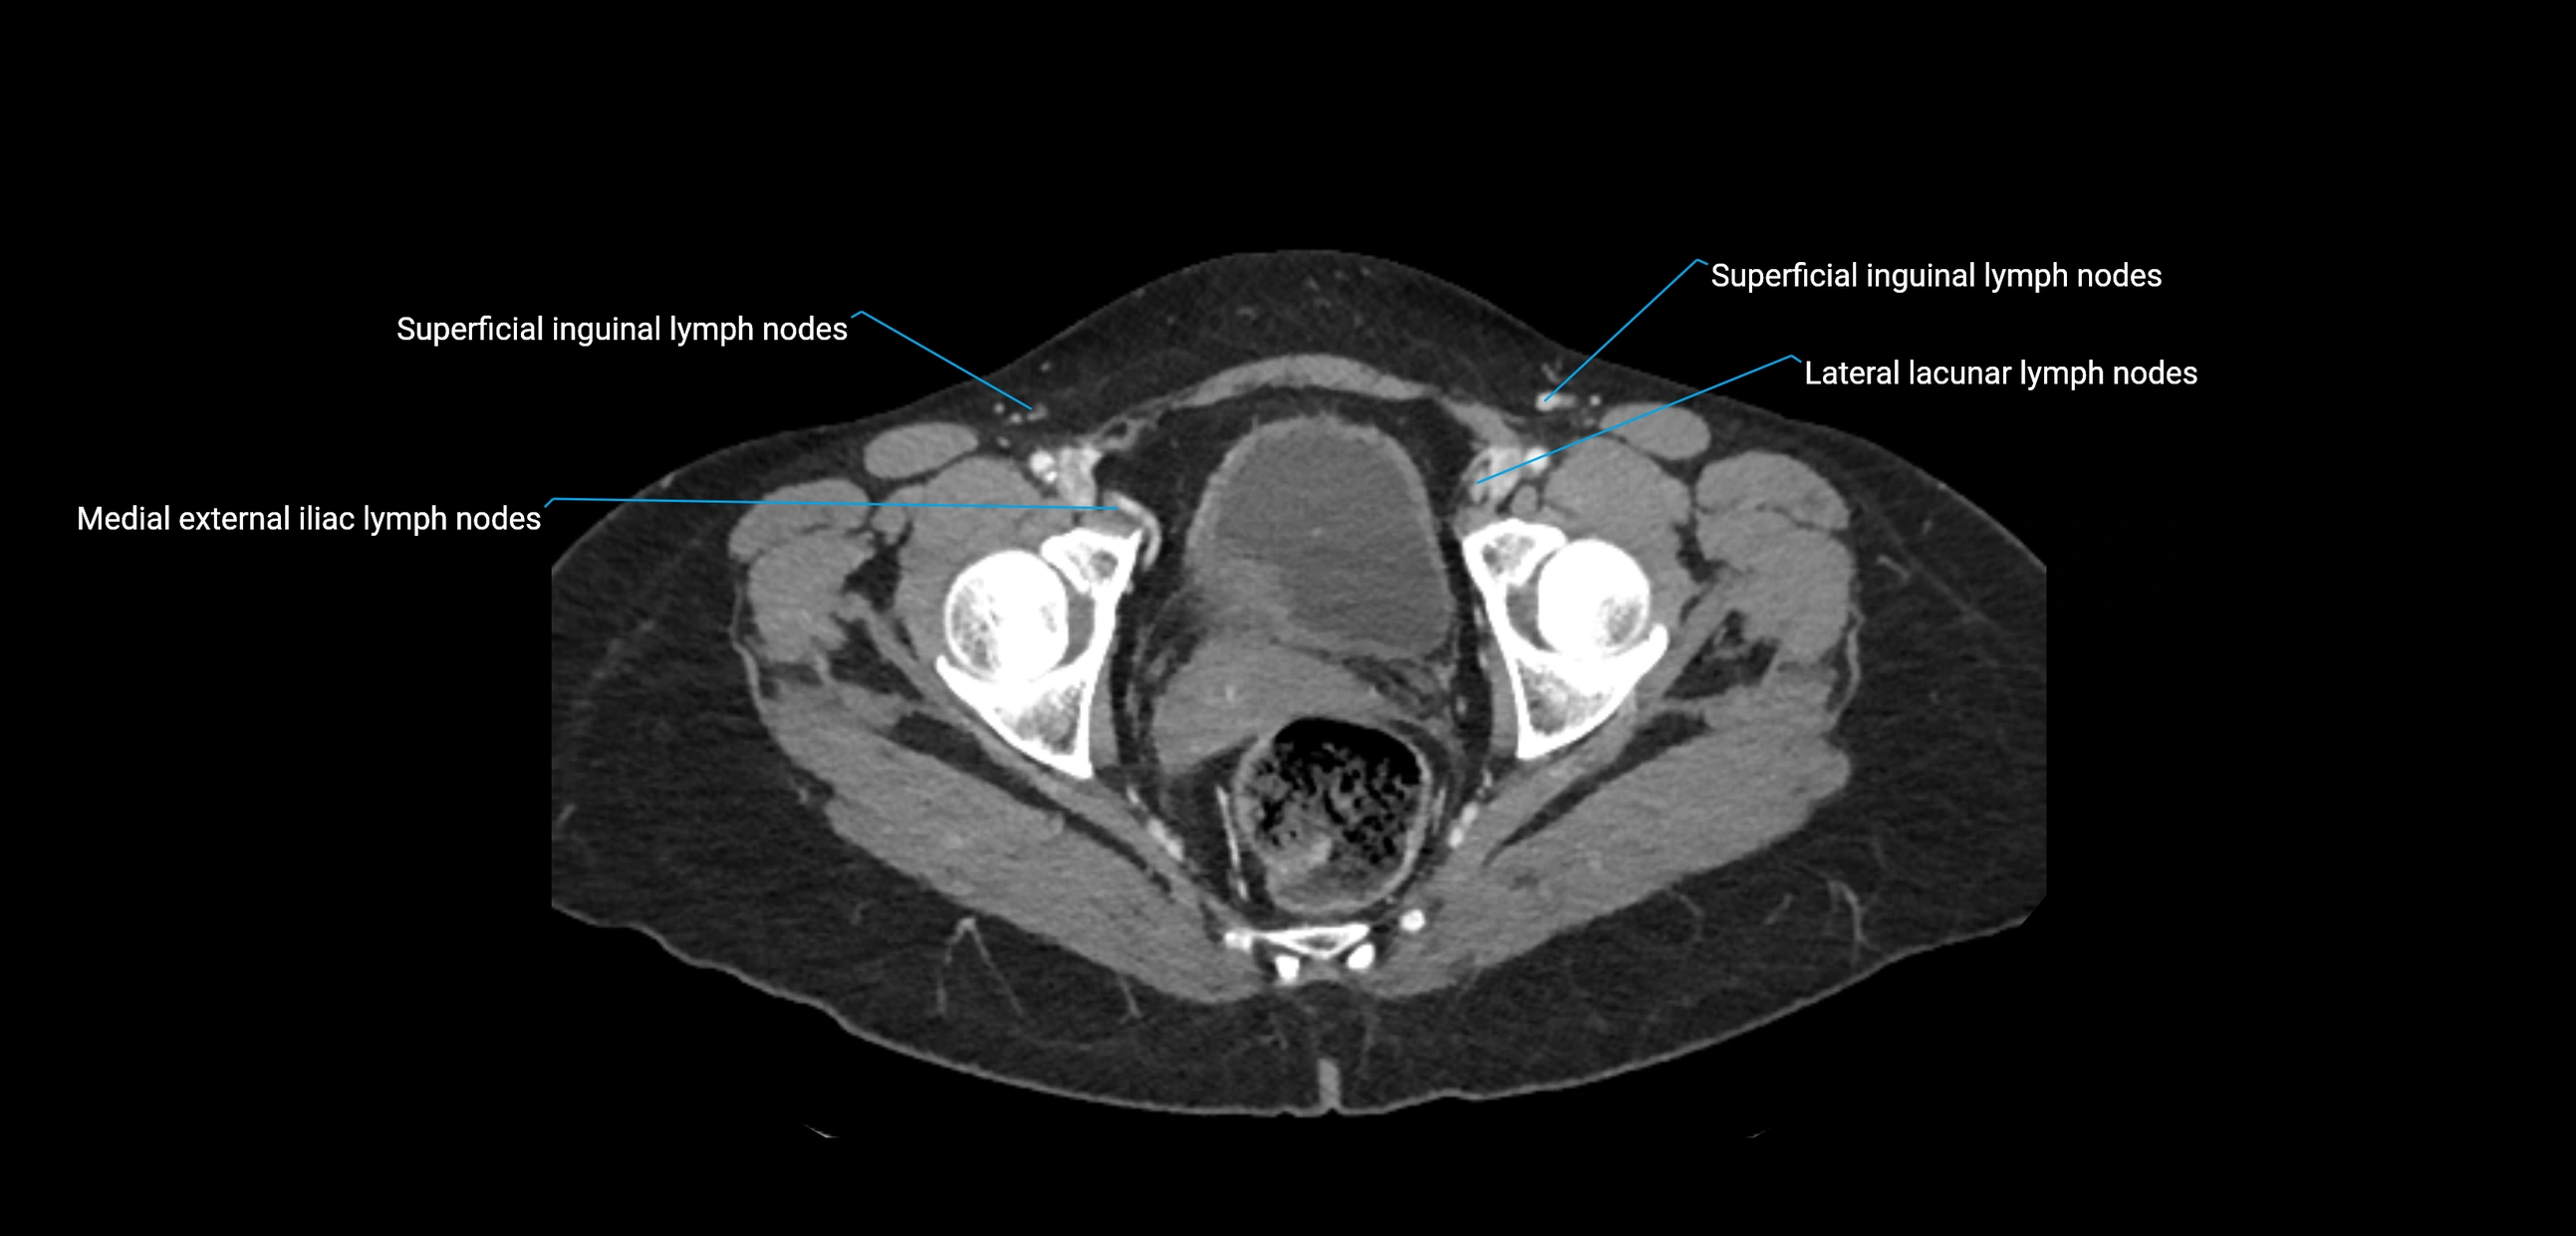

CT Appearance

CT Pre-Contrast:

• Nodes appear as soft-tissue density nodules adjacent to the aorta and IVC

CT Post-Contrast:

• Normal nodes enhance homogeneously

• Malignant nodes may show heterogeneous enhancement, central necrosis, or conglomerate formation

• Size >1 cm short axis is suspicious, though morphology and distribution are equally important